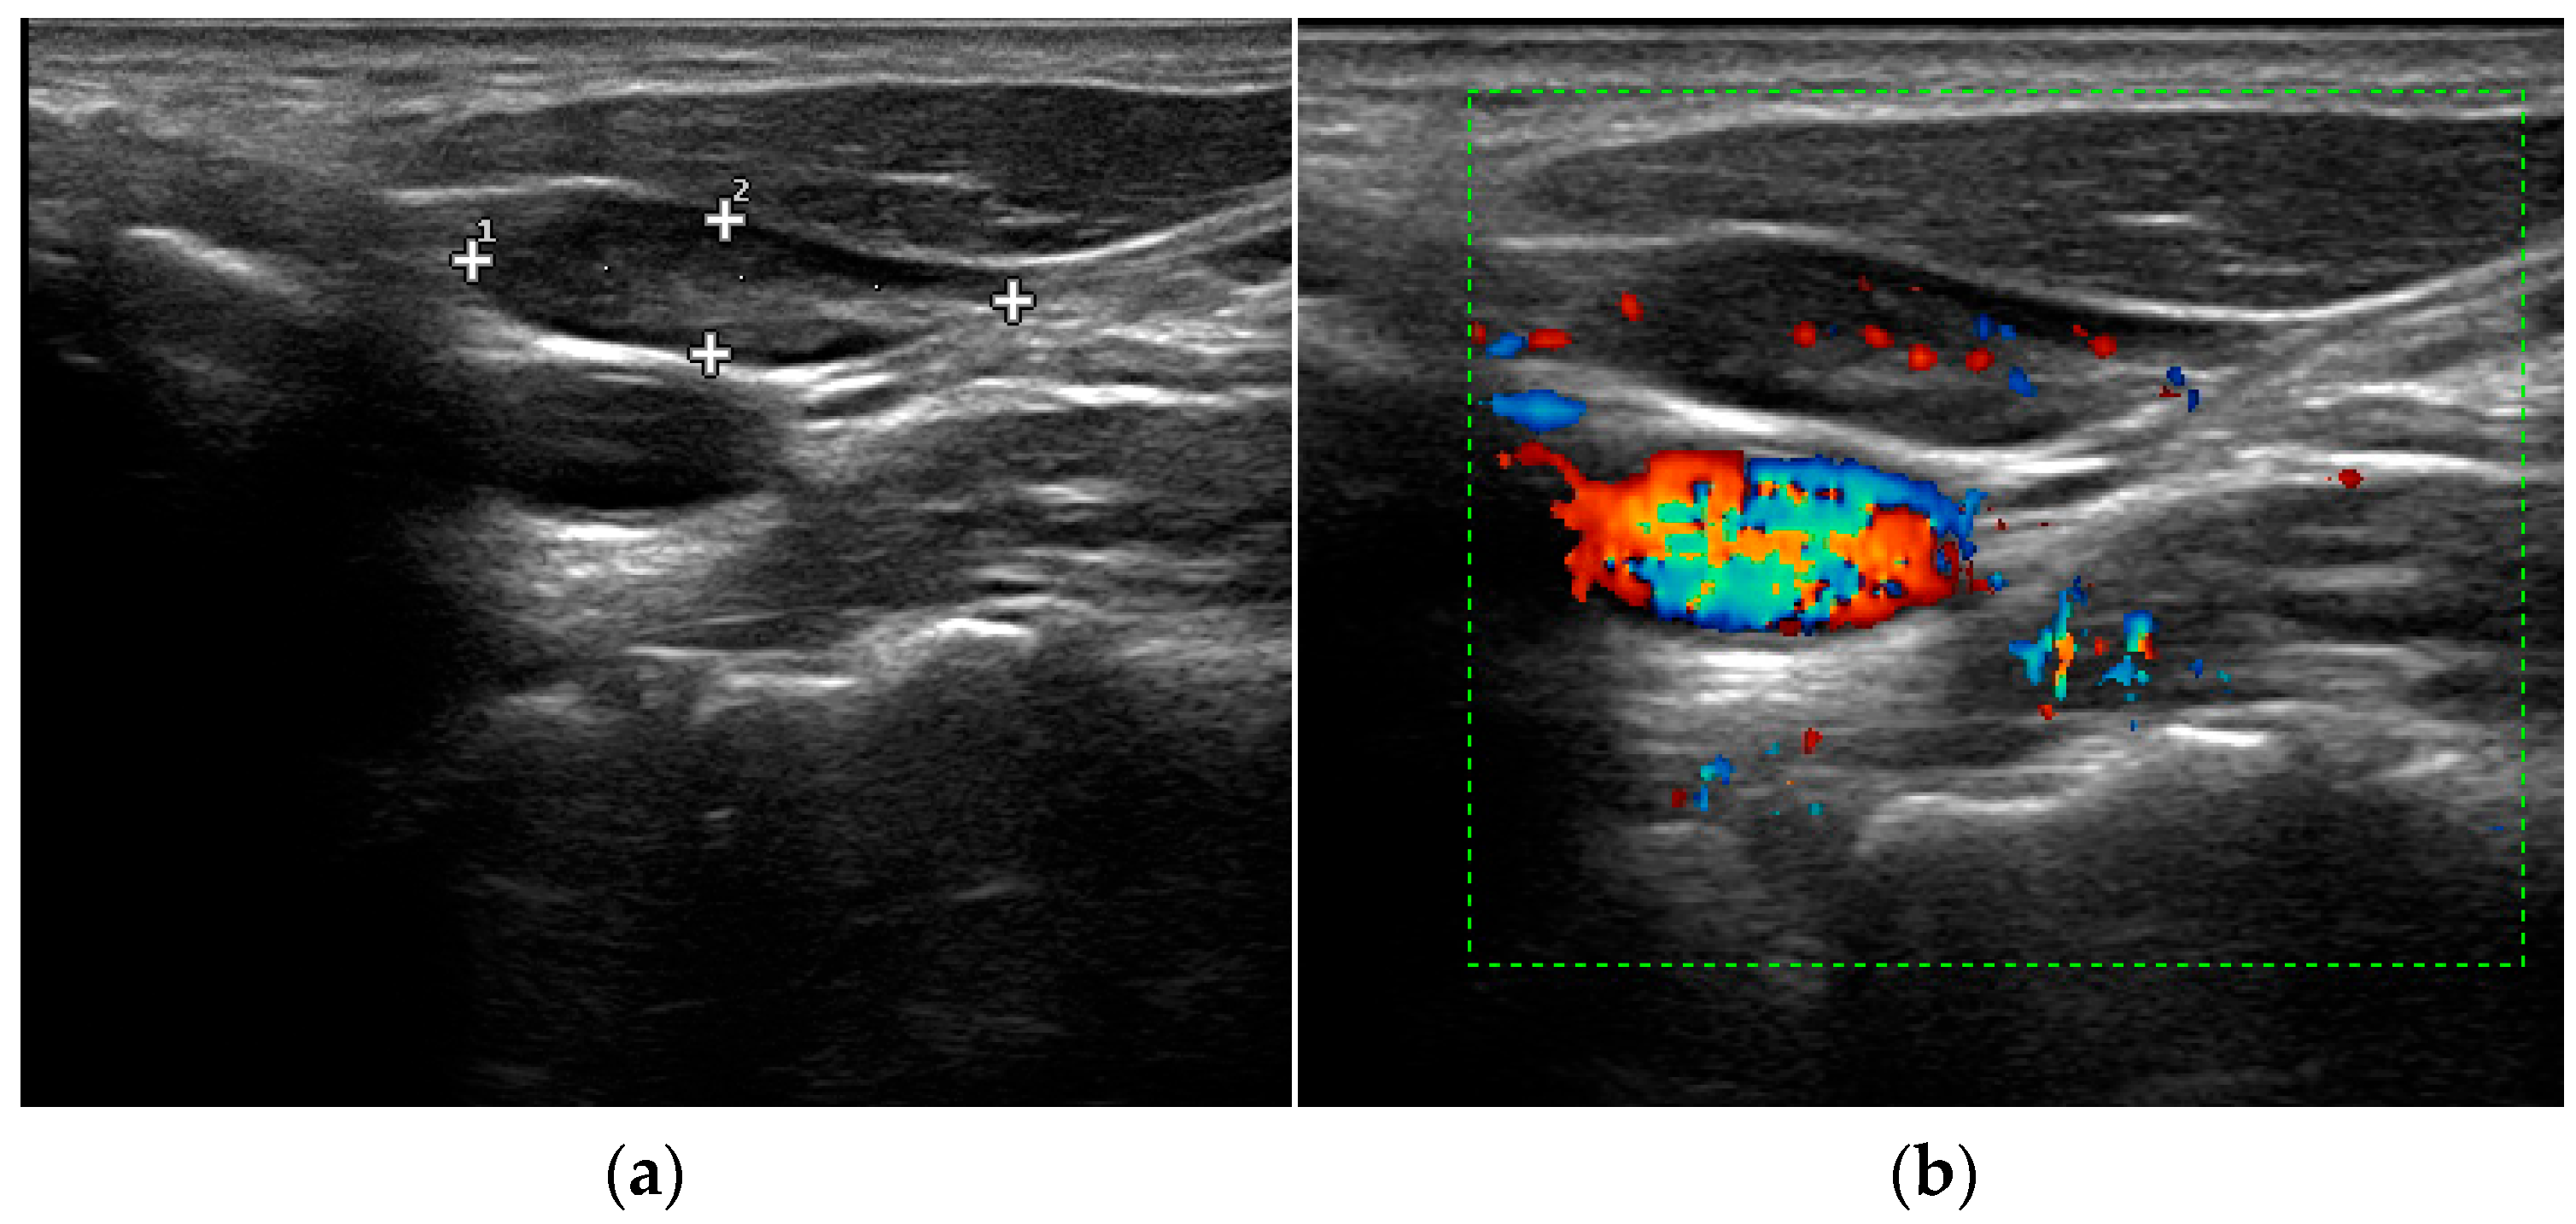

Understand the critical differences between the thyroid and parathyroid glands. Discover how these endocrine organs regulate metabolism, calcium levels, and hormonal balance. This comprehensive guide explains common disorders, symptoms, and essential treatments for thyroid and parathyroid health, helping you identify potential issues and when to consult an endocrinologist for specialized endocrine care.